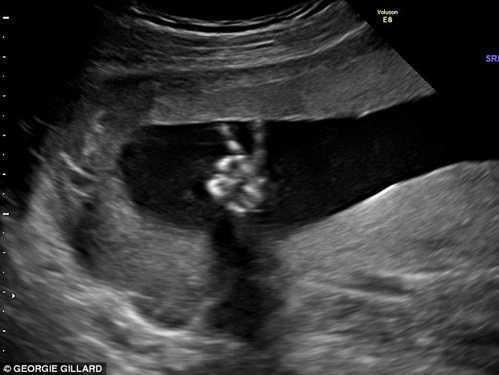

Một gia đình người Anh đã hết sức ngạc nhiên khi nhận được kết quả siêu âm cho thấy hình ảnh thai nhi biết "tạo dáng chữ V" trong bụng mẹ.